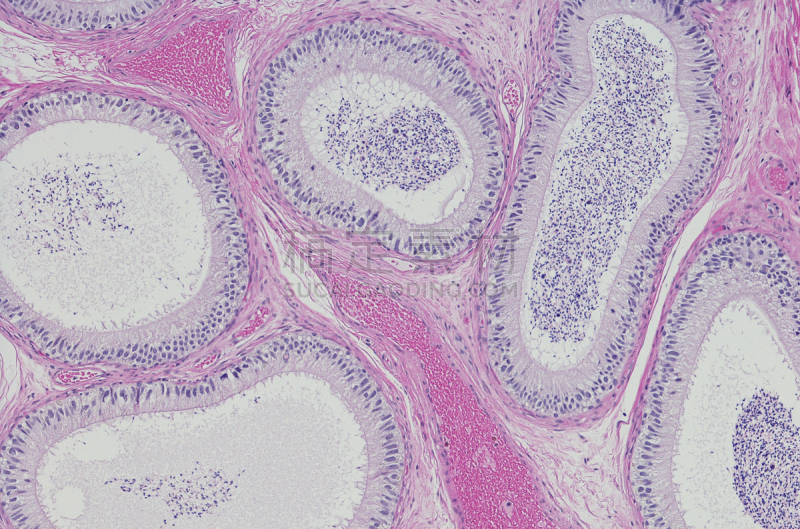

显微镜下的人类细胞详情

JPG